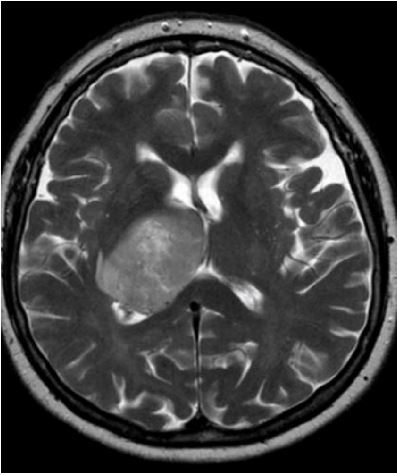

15

Q

-imaging modality -weight -orientation -window -body part -iv contrast -abnormality

A

-MRI -T2 -axial -brain -brain -cant tell -glioblastoma multiforme

How well did you know this?